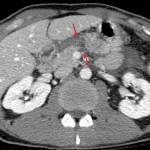

- Pancreatic laceration with complete parenchymal disruption in the proximal body and surrounding fluid/hematoma

- Pancreatic injury

Pancreatic laceration with complete parenchymal disruption in the proximal body and surrounding fluid/hematoma. Findings raise concern for pancreatic duct disruption.